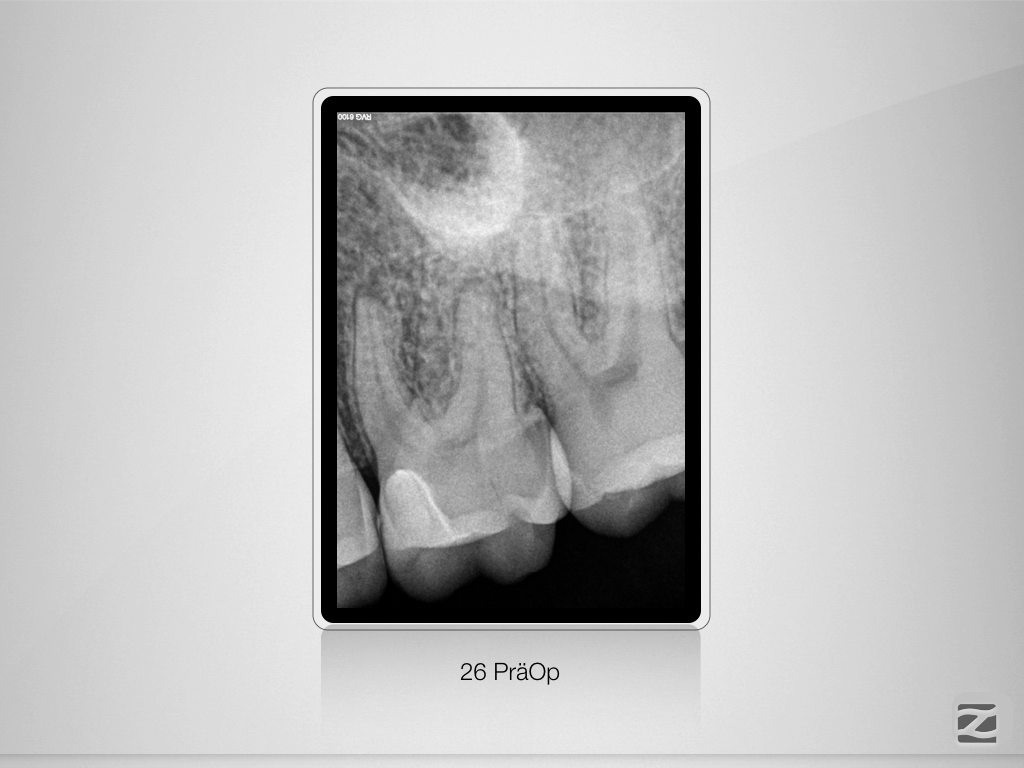

26D.001

Fluch und Segen!